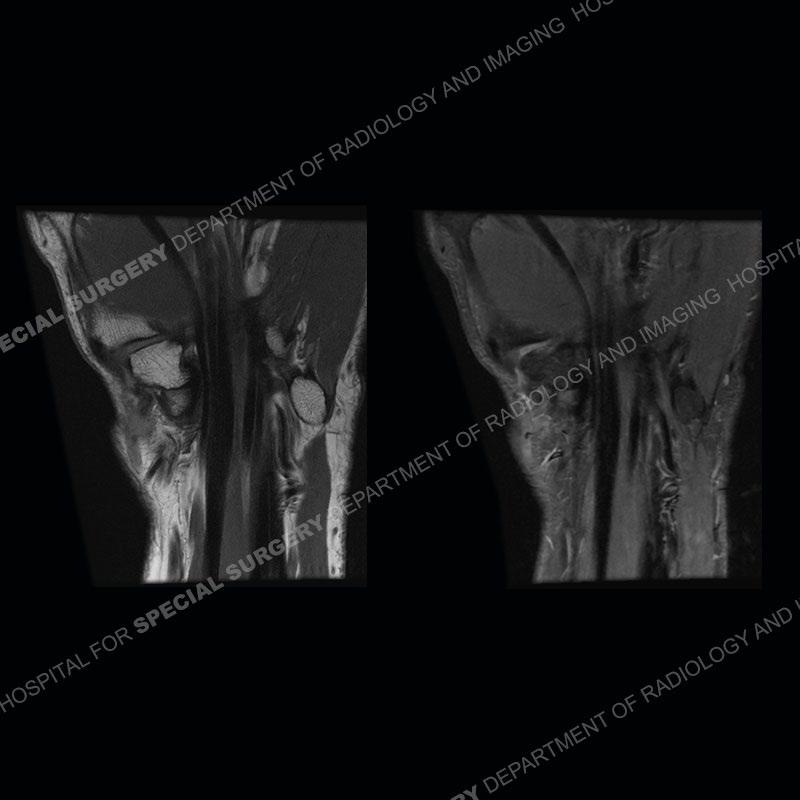

The radiographs in this case are not particularly contributory. The MRI demonstrates tenosynovitis of the first extensor compartment manifest by fluid/synovitis distention of the tendon sheaths. Multiple tendon slips are present of the abductor pollicis longus (APL) and with severe tendinosis seen of one of the tendon slips. Other areas of slightly increased signal and tendinosis are present of the components of the APL. Noted is a somewhat prominent septum separating the more dorsal extensor pollicis brevis (EPB) from the APL.

This case in particular highlights some of the normal variants of the first extensor compartment which can be confusing as well as clinically important. The APL can have multiple tendon slips with the insertion mostly being to the base of the thumb metacarpal but with additional insertions found of the trapezium and occasionally other thenar muscles. With additional tendinosis and partial tearing, this can become particularly confusing.